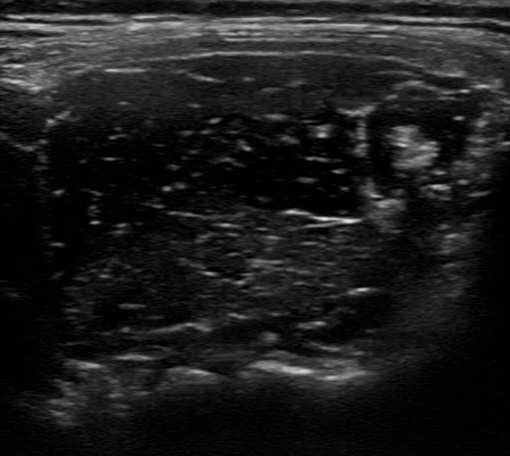

肩こりへの超音波エコーガイド下鍼

肩周囲の筋肉や神経をエコーで確認し、こりや痛みの原因部位へ的確に鍼を行います。深部の慢性肩こりにも対応します。